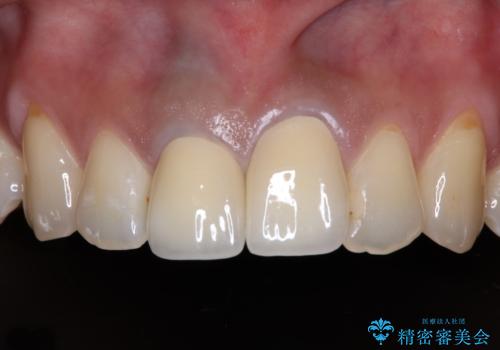

根管治療後のクラウンも、まるでもとの自分の歯のように自然な仕上がりとなり、患者様には大変満足していただけました。